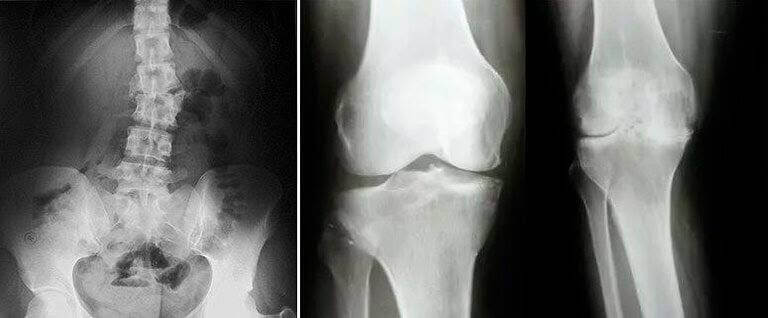

Касалхонада таҳлил олишди. Ёшгина яхши шифокор қўлига тушдим, лекин у ҳам: “Кечирасиз, биз сизни оёққа туролмаймиз, бўғимларингиз аллақачон емирилиб бўлган, яллиғланишни тўхтатамиз. Умуман олганда, юролмайсиз, протез қўйдиришингиз керак”, деди.

Умуртқам ҳам ёмон аҳволда экан. Шифокор ногиронликни расмийлаштираверинг, деди.

Шундан сўнг ўзим касалхонага бордим, у ердаги шифокорлар ҳайратдан бақа бўлиб қолишди. Улар мени МРТга олиб боришди, ҳамма нарсани кўриб чиқишди. Кейин бир шифокор, афтидан, биринчи суратлар яроқсиз чиқди, деди, чунки артрит даволанмас эмиш. Лекин менда артритни топишолмади-ку! Мен шунчаки жилмайиб қўя қолдим.